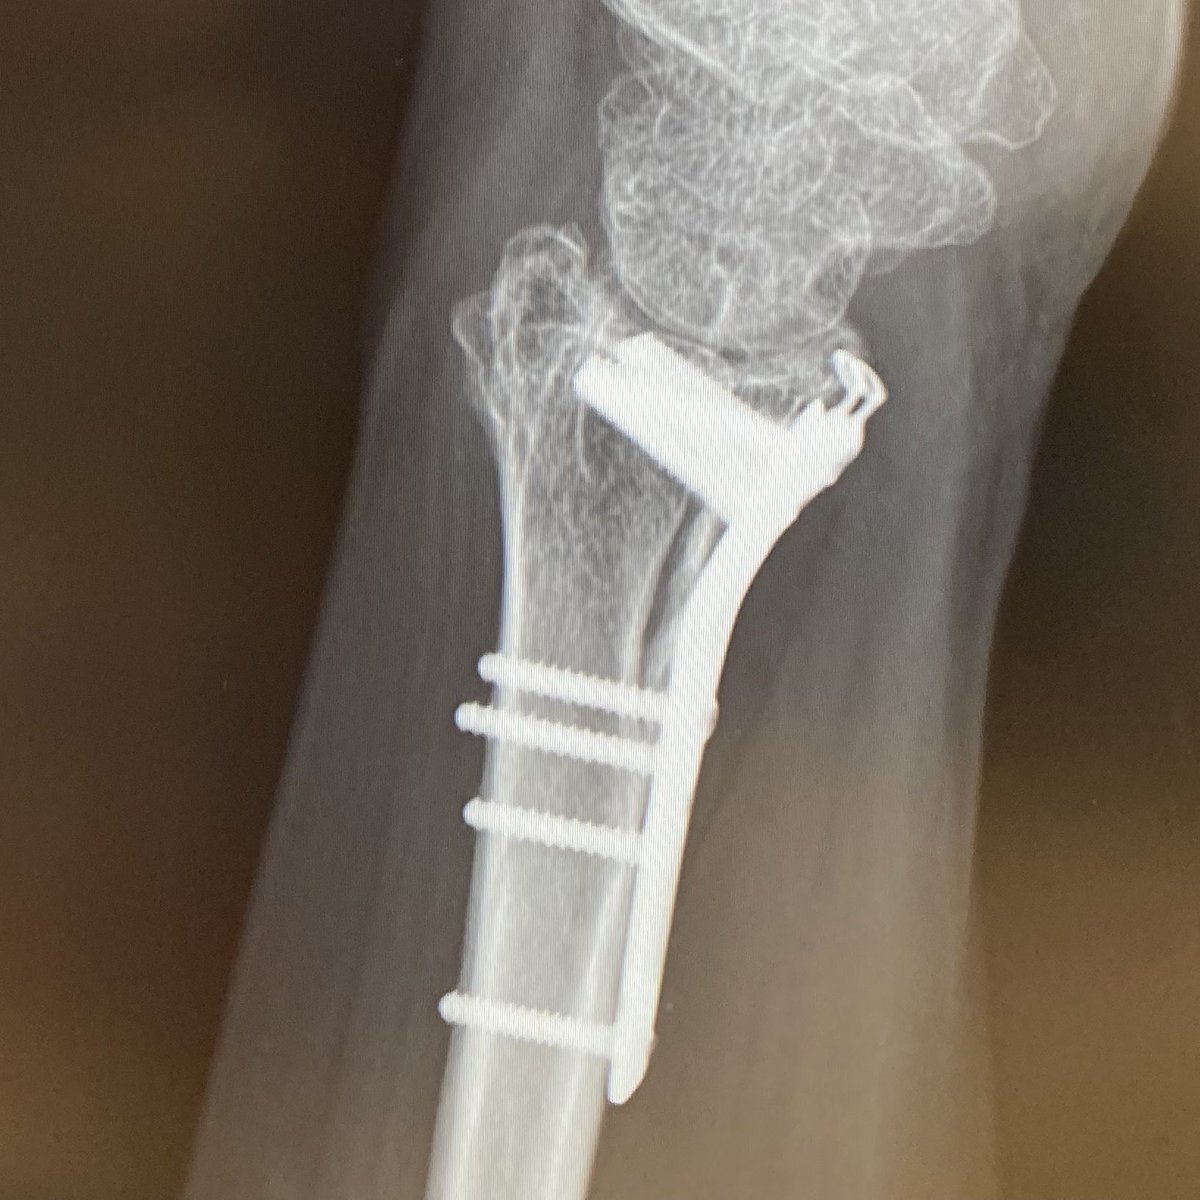

橈骨の抜釘手術(プレート除去)は来年1月になった。できれば年内にやりたかったな🥹 #橈骨遠位端骨折(粉砕) pic.x.com/oatzTfRtxU